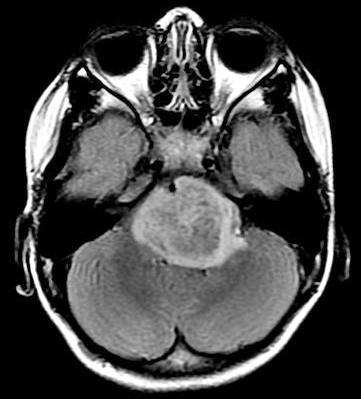

DIPG typically attacks children 4 to 9 years of age. Children progressively lose muscle control as the tumor rapidly attacks the pons, a region deep inside the brain that connects the brain to the spinal cord, and is difficult to reach and surgically remove. Despite radiation treatment, children usually survive for about nine months, and less than 1 percent survive longer than five years.

Six years ago, Dr. Monje started to create and share cell cultures of patients' DIPG cells that could be studied in labs. In this study, she and her colleagues used cell cultures collected from 16 patients in the United States and Europe to search for drugs that could kill or stop the growth of DIPG cells. By performing experiments in petri dishes and with mice, they found that panobinostat, a drug designed to change the way cells regulate genes, may be effective at inhibiting DIPG growth and extending survival rates.